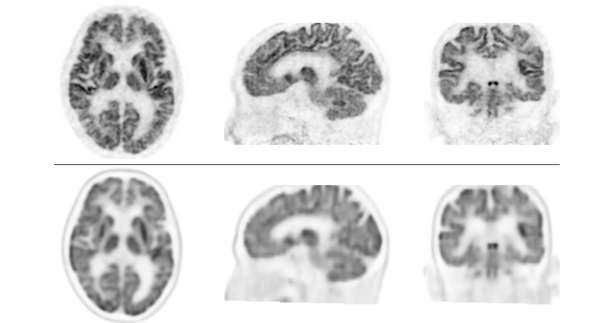

検証では、認知機能障害、てんかん等の18名の患者において、脳FDG-PET装置を用いて撮像した画像と、本PET装置で撮像した画像を比較しました。次に、認知機能障害患者17名において、従来のPET/CT装置を用いた画像と本PET装置で撮像した画像を比較しました。その結果、全例において本PET装置による画像の分解能が優れており、従来型よりも分解能が高く、細かいところまで描出できることが示されました。